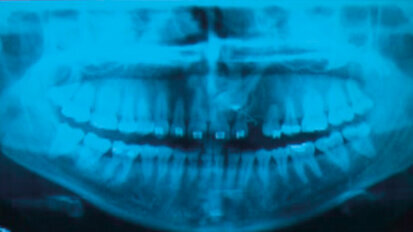

Carie e brown spot: il recupero dell’estetica del sorriso tra debridment, sbiancamento, infiltrazioni, ricostruzioni. Case report

Le tecnologie avanzate permettono la scelta di percorsi terapeutici personalizzati per ogni esigenza clinica ed emotiva. Progettare protocolli operativi ...